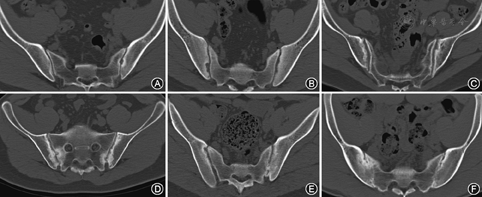

选择在骶髂关节病变性质评价中可见异常的骶髂关节CT影像,包括可疑异常、单侧骶髂关节炎和双侧骶髂关节炎,应用下述标准进行分级评价。(1)1984年修订的AS纽约分类标准骶髂关节炎X线分级标准[12](以下简称"NY标准" ):0级:正常;1级:可疑异常;2级:局限性骨侵蚀或骨硬化;3级:中重度骶髂关节炎,出现以下1项或多项:骨侵蚀、骨硬化、关节间隙增宽或狭窄、部分强直;4级:完全强直。(2)Lee等[13]制订的骶髂关节炎螺旋CT分级标准(以下简称"Lee标准" ):0级:正常;1级:局限性骨侵蚀仅见于单个层面;2级:骨侵蚀见于<25%的层面,不伴关节间隙改变;3级:骨侵蚀见于≥25%的层面,伴有关节间隙改变和(或)部分强直;4级:完全强直。(3)因斯布鲁克骶髂关节炎高分辨率CT分级标准[14] (以下简称"Innsbruck标准" ):Ⅰ(A)级:关节间隙>4 mm;Ⅰ(B)级:关节间隙<2 mm;Ⅱ(A)级:关节面不规则;Ⅱ(B)级:骨侵蚀;Ⅲ(A)级:软骨下骨硬化;Ⅲ(B)级:骨赘形成;Ⅳ(A)级:骨桥形成;Ⅳ(B)级:关节强直。

(1)NY标准:509例患者1 018例骶髂关节中,0级26例,1级81例,2级103例,3级620例,4级188例,3级和4级共占比79.37%。(2)Lee标准:509例患者1 018例骶髂关节中,0级67例,1级31例,2级76例,3级656例,4级188例,3级和4级共占比82.91%。(3)Innsbruck标准:509例患者1 018例骶髂关节中,Ⅱ(A)级109例,Ⅱ(B)级91例,Ⅲ(A)级273例,Ⅲ(B)级213例,Ⅳ(A)级103例,Ⅳ(B)级188例,Ⅲ级和Ⅳ级共占比76.32%。

比较509例患者1 018例骶髂关节的NY标准和Lee标准分级评价(表1),二者一致性高(k=0.767,P<0.01)。分别比较509例患者1 018例骶髂关节的Innsbruck标准与NY标准、Lee标准分级评价(表2,表3),相关性均较好(NY标准:r=0.866,P<0.01;Lee标准:r=0.839,P<0.01)。见图3。

本研究发现,3级关节在NY标准和Lee标准中占比过大,分别占60.90%和64.44%。而Innsbruck标准将从骨质微小侵蚀所致的关节面不规则到形成关节强直前的总计占比77.50%的关节(大致相当于NY标准和Lee标准1~3级),分为从Ⅱ(A)级到Ⅳ(A)级的5个等级,分别占10.71%、8.94%、26.82%、20.92%和10.12%。这一数据表明,Innsbruck标准可更好区分不同病变严重程度的骶髂关节,有利于在随访中通过对比多次骶髂关节CT影像分级来判断病情严重程度及疾病进展速度。此外,理想的分级标准应根据骶髂关节炎病变进展过程制订。AS发病初期骶髂关节CT影像主要表现为沿关节面形成的骨侵蚀,继而在侵蚀区周边出现局灶性软骨下骨硬化,随着炎症进展,骨质不断硬化、增生,逐渐在韧带与骨关节面连接处形成骨赘,其后两侧骨赘逐渐增大、相连形成骨桥,同时关节间隙逐渐变窄,最终骨桥扩大、融合形成骨性强直。Innsbruck标准按照病情进展的先后顺序,将上述不同性质的病变分别定义为Ⅱ(A)级到Ⅳ(B)级的6个级别,更符合AS骶髂关节病变的进展特点。但应注意的是,Innsbruck标准也存在界定模糊的不足。首先,Ⅰ(A)级和Ⅰ(B)级被分别定义为关节间隙>4 mm和<2 mm,并未说明关节间隙2~4 mm时应属何种分级。同时研究显示,40岁以上正常人群中79%的骶髂关节间隙<2 mm,这意味着Ⅰ(A)级和Ⅰ(B)级关节的区分并无诊断价值。另外,该标准也未指出达到何种分级可以诊断。